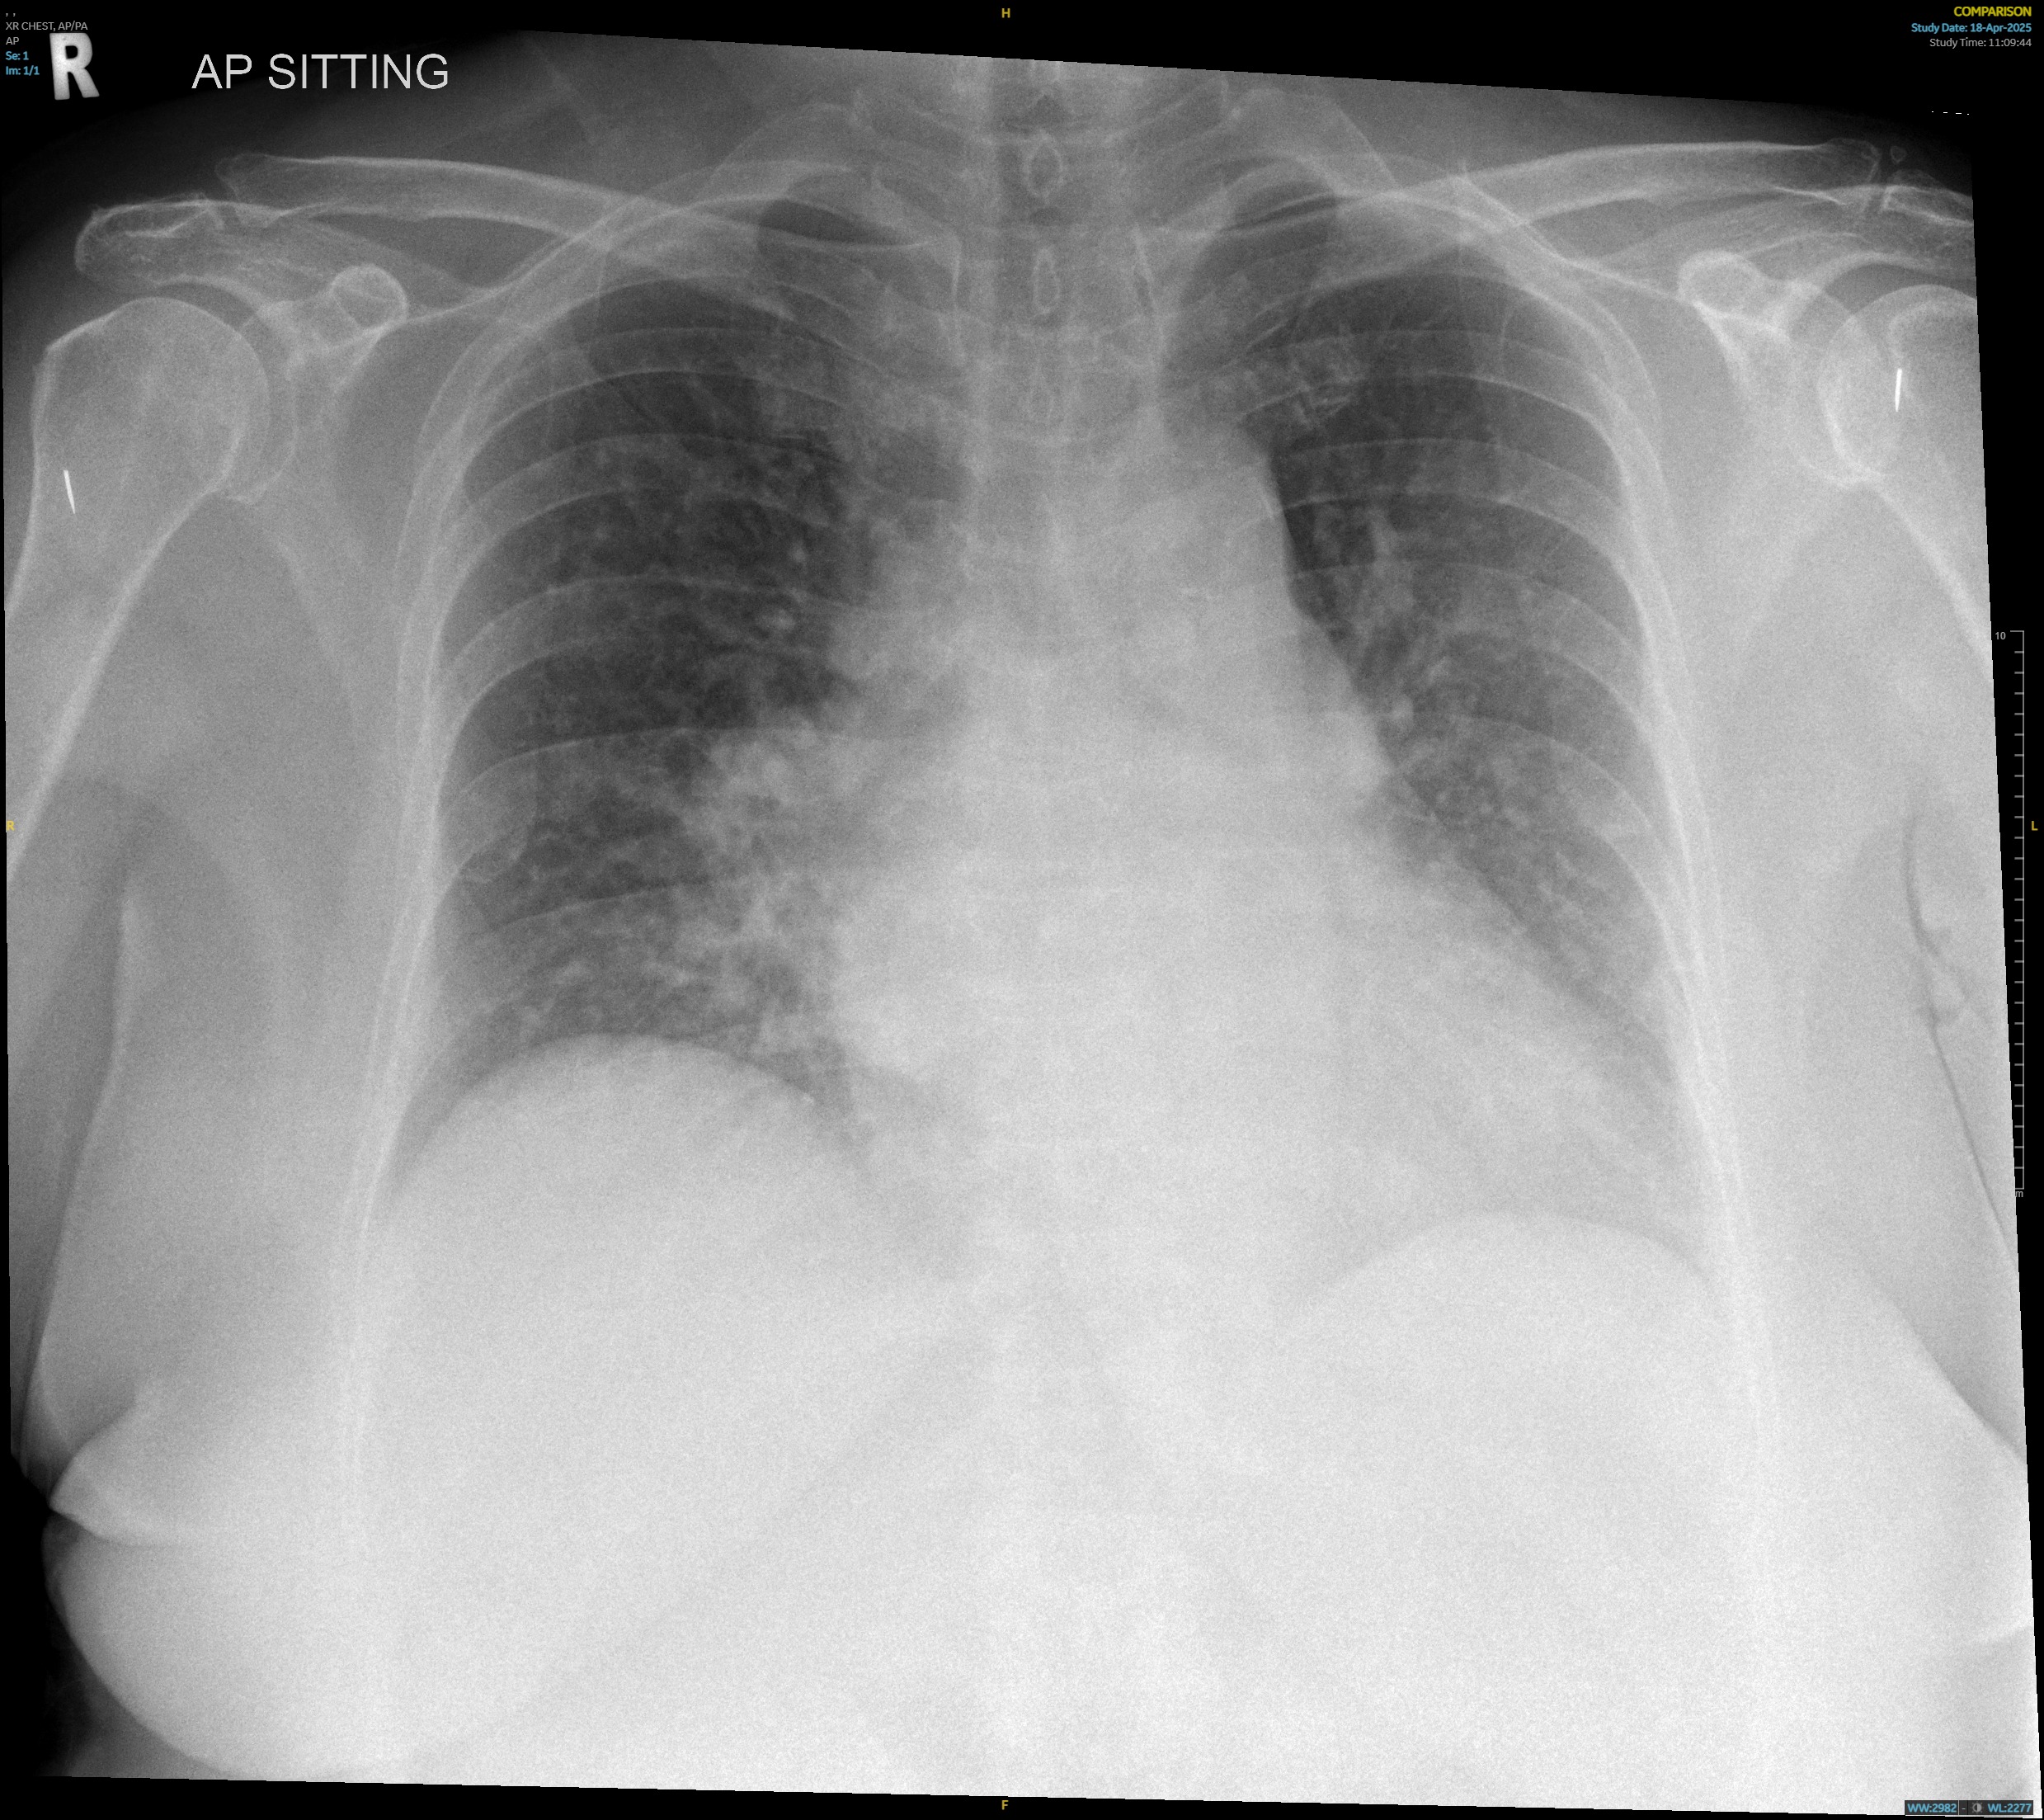

Troponin T continued to uptrend post-intubation and repeat12-lead electrocardiogram (ECG) showed worsening widespread depressions withAVR elevation. Chest X-Ray post-intubation showed rapidly worsening bilateralinfiltrates compared to admission. Bedside ultrasound showed a severely reducedleft ventricular ejection fraction.